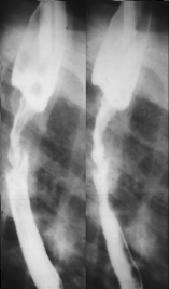

Image

radiologique de tuberculose de oesophage en TOGD :

Bord de oesophage est crenele par des petites

ulceres . Deux diverticule a type traction au tier

superieure de oesophage . |

Image TOGD

du diverticule de type traction de oesophage

associe de images creneles de ulcere multiple au

bord de oesophage . |

Image de oesophagite en TOGD ++

double de contrast . Image en crenele en ce cas se

voyaient tres net . Image de diverticule de type

traction avec retention de baryte en niveau . |